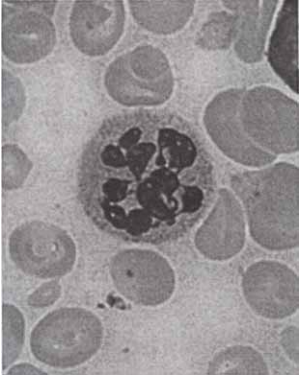

23 若在周邊血液抹片觀察到大量如圖所示的細胞,則此人比較可能得到下列何種疾病?

(A) large granular lymphocytic leukemia (B) adult T-cell leukemia/lymphoma (C) prolymphocytic leukemia (D) hairy cell leukemia